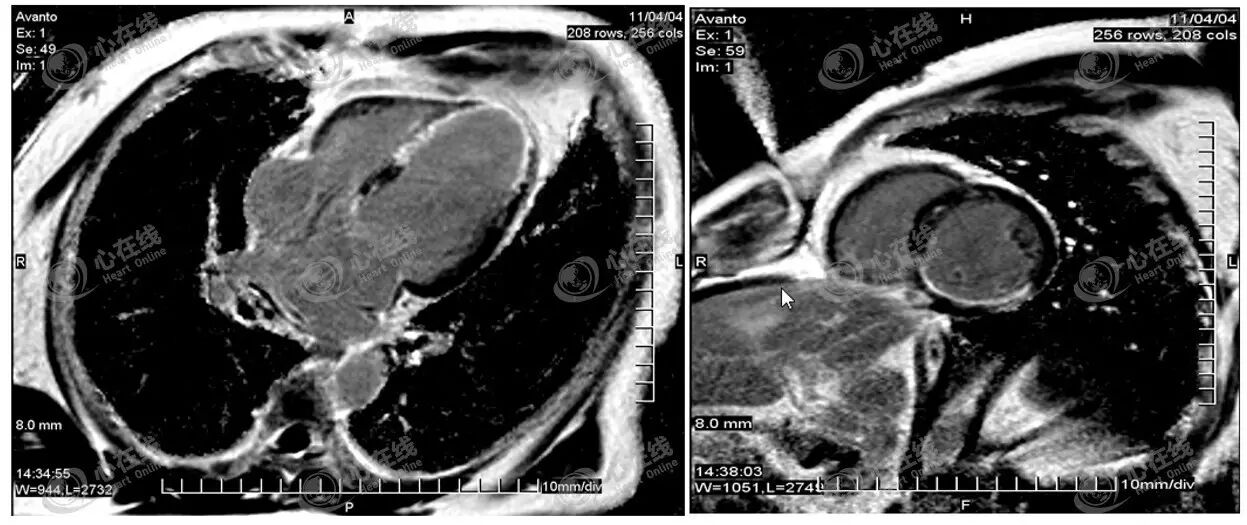

1)心肌灌注。主要评估心肌缺血情况。如图5患者,在左图静息状态下,心脏充盈较均衡,未见明显心肌缺损;在右图药物负荷状态下,左室下壁及室间隔后部可见信号强度明显减低,提示右冠状动脉供血区存在狭窄。

图5